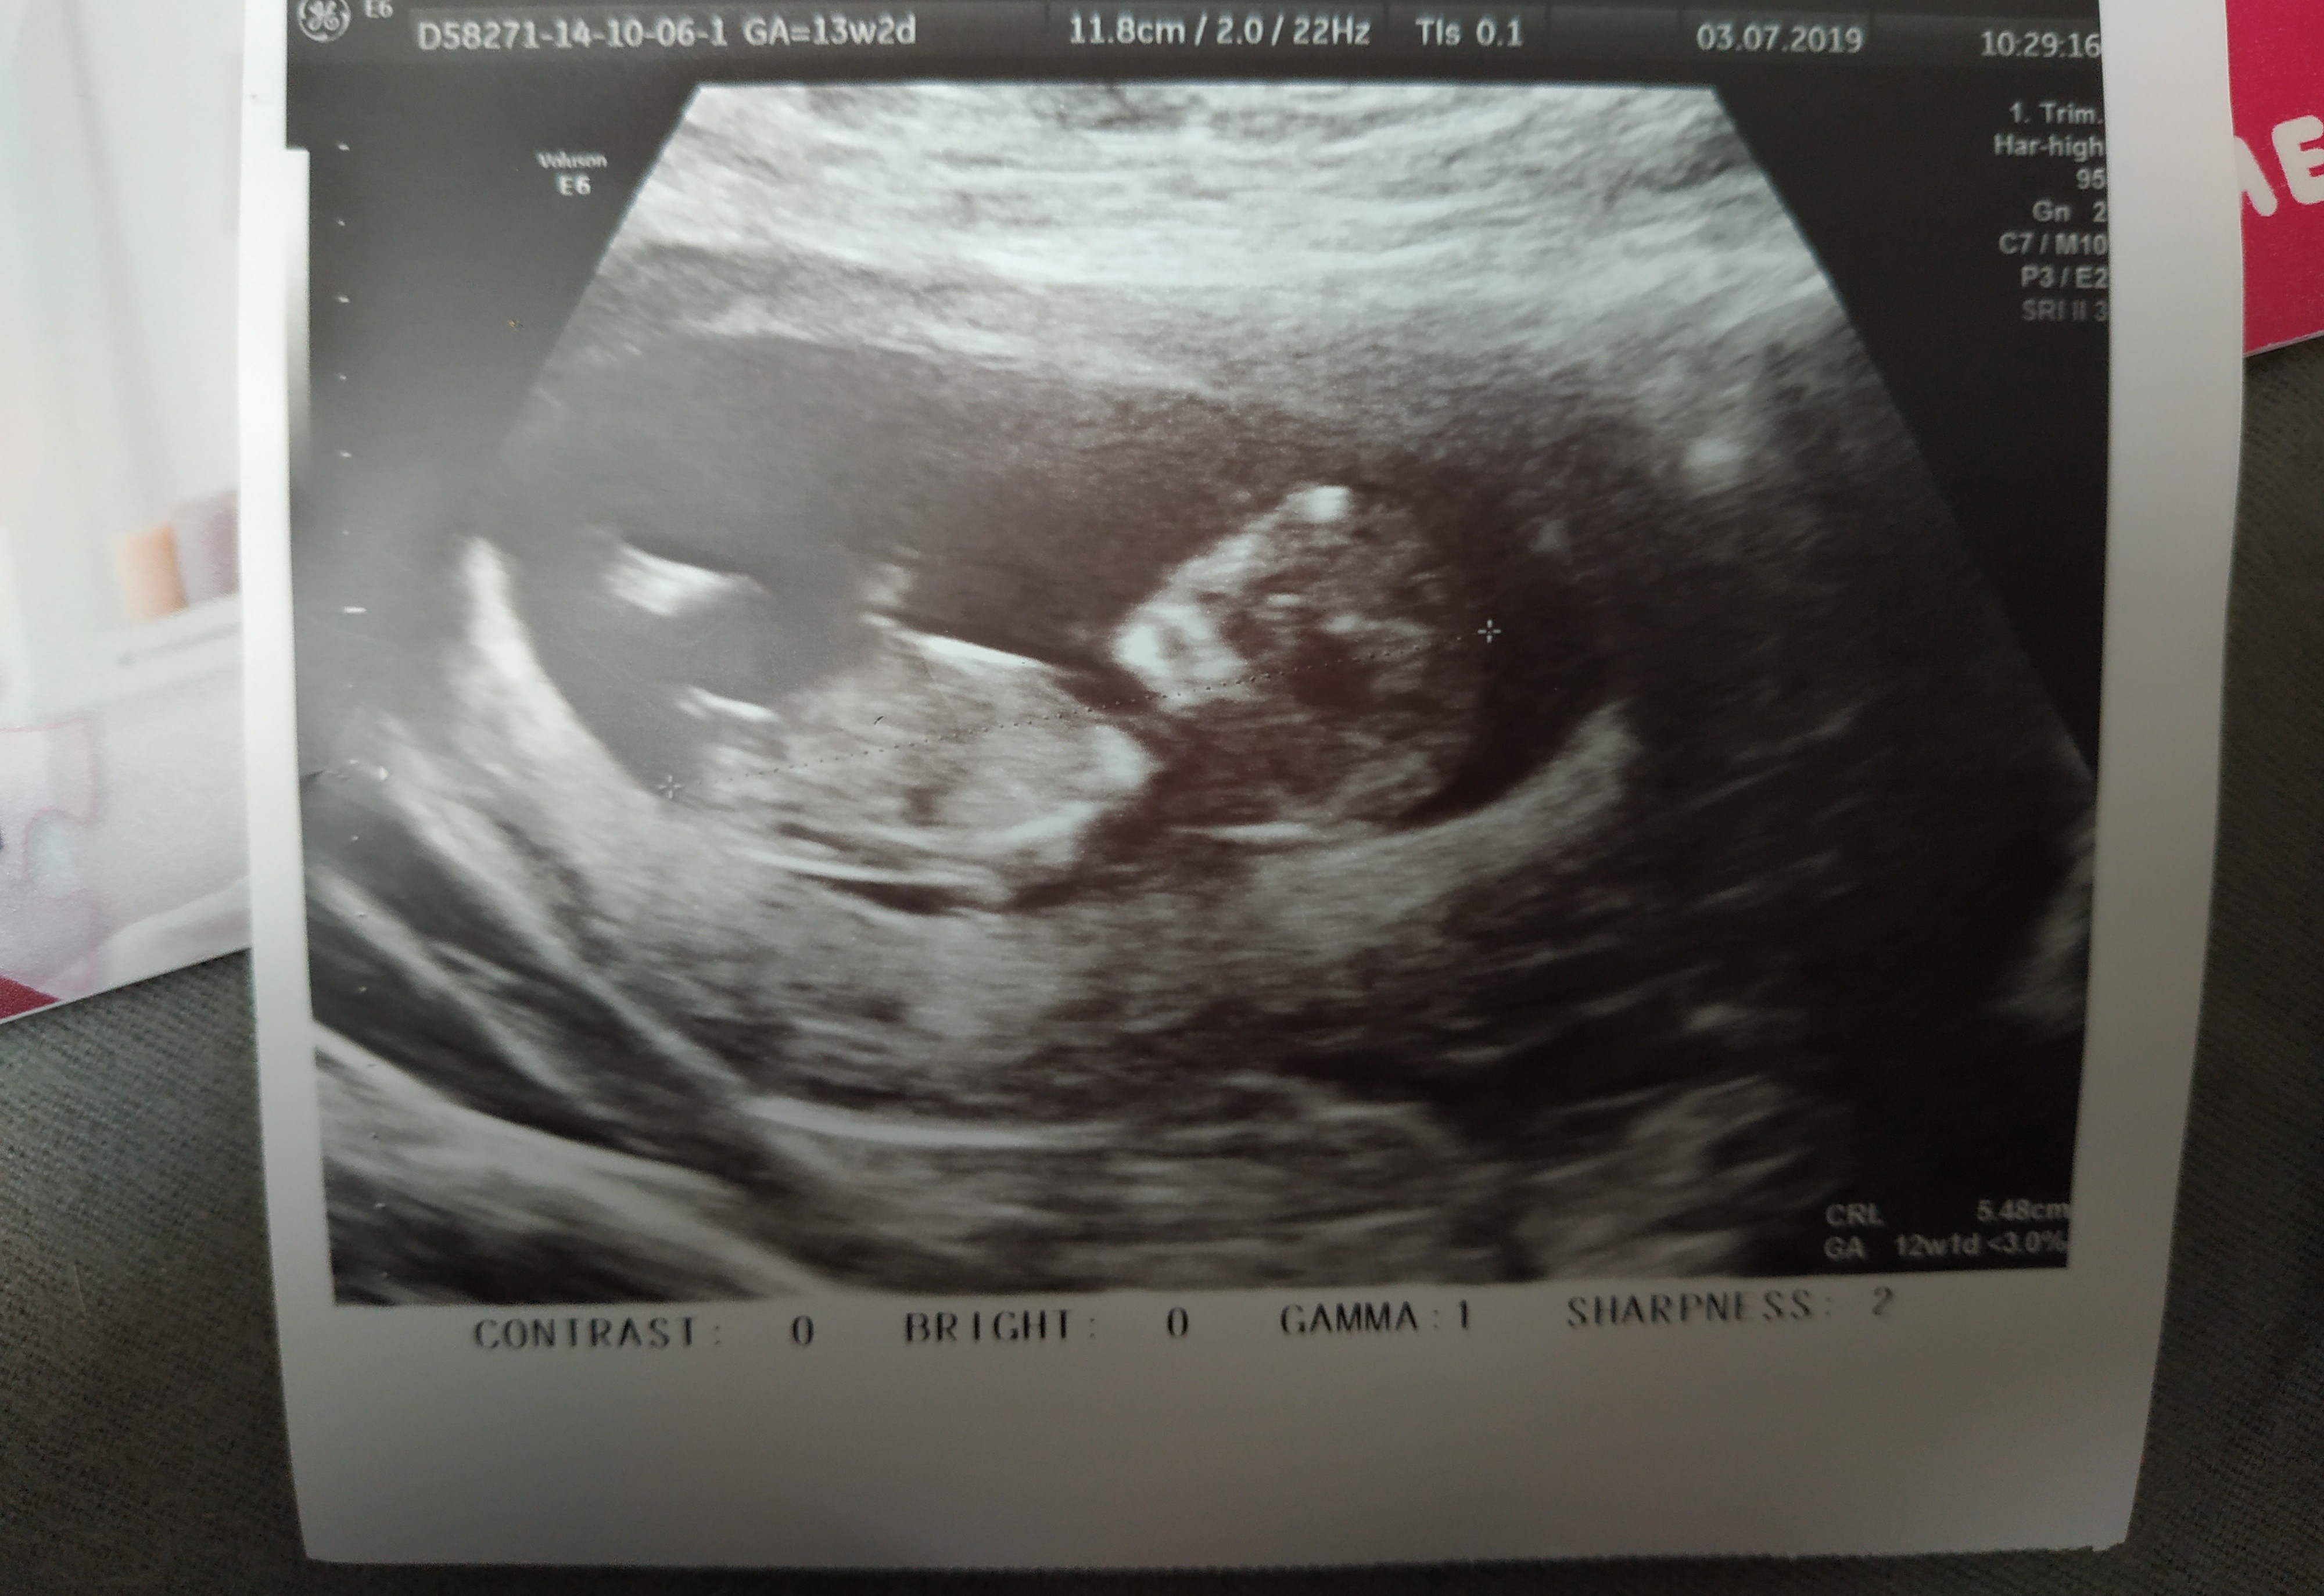

Usg chłopak czy dziewczynka

Witam w 19 tygodniu ciąży dowiedziałam się ze będę miała dziewczynkę w 20 tyg okazało się jednak , że to chłopak. Sama już nie wiem bo na jednym usg widać na pewno dziewuche a na drugim chłopca. Może to pempowina ?? Może ktoś mi pomoże rozwiązać ta zagadkę

• 4A8F5FF1-76CA-4DE0-AC12-5EDF08E820F2.jpg

4A8F5FF1-76CA-4DE0-AC12-5EDF08E820F2.jpg

596,4 KB · Wyświetleń: 45 230